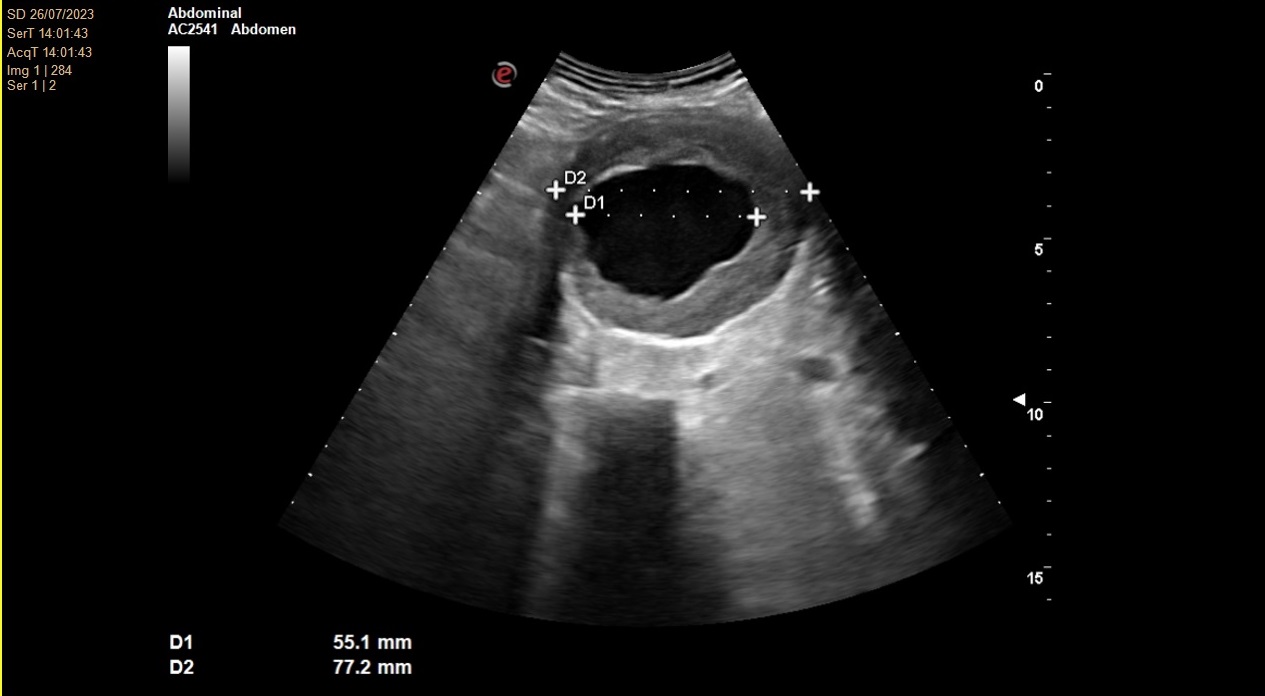

No se consigue visualizar el lóbulo hepático izquierdo ni páncreas por interposición de gas intestinal. Lóbulo hepático derecho de ecogenicidad y ecoestructura normal. Vesícula biliar de paredes finas y lisas sin contenido en su interior. Vía biliar no dilatada. Se visualiza una arteria aorta a nivel abdominal de un tamaño de 78 x 77 mm en su diámetro máximo.

Angio TC toracoabdominal en el que se observa una dilatación aneurismática de 73,8 mm de morfología fusiforme infrarenal hasta bifurcación ilíaca con trombosis mural concéntrica en toda su extensión.

Aneurisma de aorta abdominal.